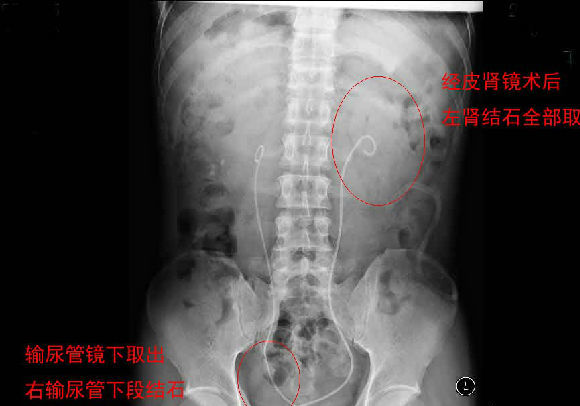

每天早上手術(shù)間響起泌外醫(yī)生們特有的交談聲音和機(jī)器們互相的運(yùn)轉(zhuǎn)聲交替成了一道熟悉不變的旋律,從手術(shù)室護(hù)士擺著各種專用體位,推著各種器械,液體進(jìn)進(jìn)出出,醫(yī)生們應(yīng)用著各種碎石手段消滅石頭,利用氣壓彈道、激光、超聲等碎石工具,把結(jié)石擊碎取出,一陣忙碌的節(jié)奏。泌尿外科的手術(shù)時(shí)間都不長,每天手術(shù)例數(shù)又多,你就會(huì)看見這么一群人來來回回,醫(yī)生護(hù)士還是那么個(gè),病人都換了無數(shù)。最長一次從早上8點(diǎn)到隔天凌晨2點(diǎn)才結(jié)束手術(shù),回到家就立馬睡覺都顧不上吃飯?,F(xiàn)在手術(shù)間正做著一臺(tái)經(jīng)皮腎鏡下碎石取石術(shù),這是我們醫(yī)院泌外科的王牌。

經(jīng)皮腎鏡取石術(shù),就是在腰部建立一條從皮膚到腎臟的通道,通過這個(gè)通道把腎鏡插入腎臟,英文簡寫為PCNL。經(jīng)皮腎鏡取石術(shù)是腎結(jié)石治療的現(xiàn)代微創(chuàng)技術(shù),我院在惠州率先開展此項(xiàng)技術(shù),現(xiàn)在每年進(jìn)行數(shù)百例手術(shù),基本上已經(jīng)淘汰了開放手術(shù)取石。經(jīng)皮腎鏡取石術(shù)是一項(xiàng)技術(shù)性非常強(qiáng)的手術(shù)。我們知道,腎臟是血管非常豐富的器官,腎臟血流占心臟排出血量的1/4。既要盡量避免出血、又要努力取凈結(jié)石、還要保護(hù)腎臟功能,這需要非常精細(xì)的手術(shù)技術(shù)。從某種程度上說,這個(gè)手術(shù)要比治療腎癌的腎切除術(shù)難度大很多。傳統(tǒng)的“開刀取石”的方法,需要在腰部做一個(gè)的大切口,切開腰部的肌肉,把腎臟分離出來,在腎盂或腎實(shí)質(zhì)切開一個(gè)小口,將結(jié)石取出來。這種方法損傷大、出血較多、痛苦重、恢復(fù)慢。通常手術(shù)后需要住院7天以上。因?yàn)槭中g(shù)切口大,不但皮膚不美觀,而且手術(shù)后患者的體力受影響比較大。與開放手術(shù)相比,經(jīng)皮腎鏡取石術(shù)具有損傷小、痛苦輕、取石徹底、恢復(fù)快等優(yōu)點(diǎn)。腰部的切口通常小,因?yàn)椴磺虚_肌肉,不但不影響美觀,而且手術(shù)后對勞動(dòng)力幾乎沒有影響。手術(shù)后住院時(shí)間也明顯縮短。與腹腔鏡取石相比,經(jīng)皮腎鏡取石術(shù)對腎臟及周圍的結(jié)構(gòu)影響小,不影響以后的各種腎臟手術(shù)。與體外碎石相比,它的治療周期短、效果立竿見影,對腎功能的影響也較小。(手術(shù)室/麻醉科 阮伊莎)